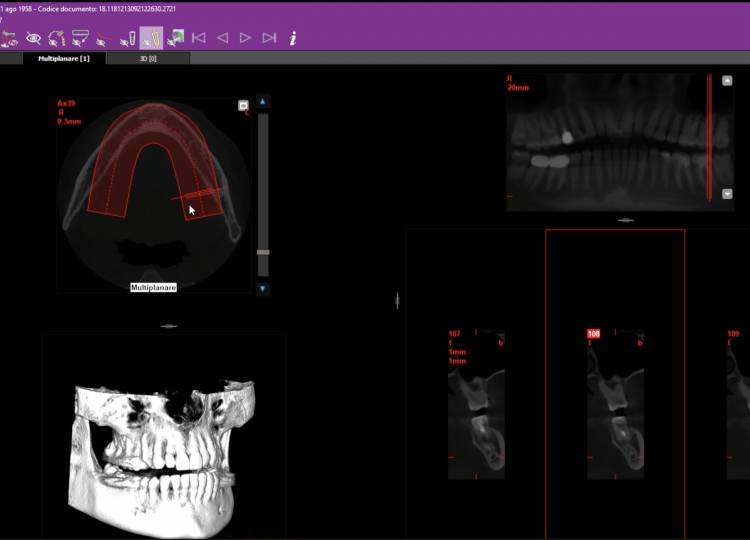

Grazie a immagini tridimensionali ottenute al computer, pianifichiamo con precisione gli interventi di implantologia, evitando rischi per la struttura anatomica della bocca e riducendo sia la durata della seduta che il periodo di guarigione post-operatoria.

Grazie a immagini tridimensionali ottenute al computer, pianifichiamo con precisione gli interventi di implantologia, evitando rischi (...)

per la struttura anatomica della bocca e riducendo sia la durata della seduta che il periodo di guarigione post-operatoria.